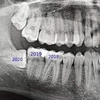

علاج الزرع السني